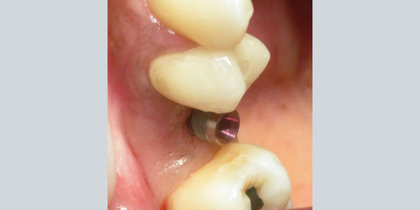

• Tooth #14 is replaced using a Glidewell HT Implant. thumbnail image

Single-Unit Posterior

Tooth #14 is replaced using a Glidewell HT Implant.